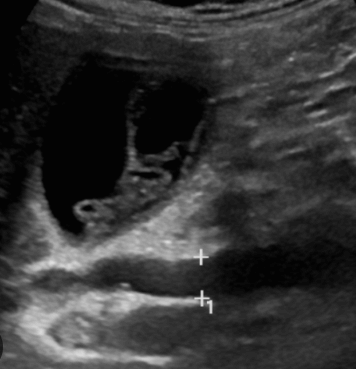

- 담관과 연결되는 많은 낭포가 있다.

- 담관 내 결석과 반사체가 보인다.